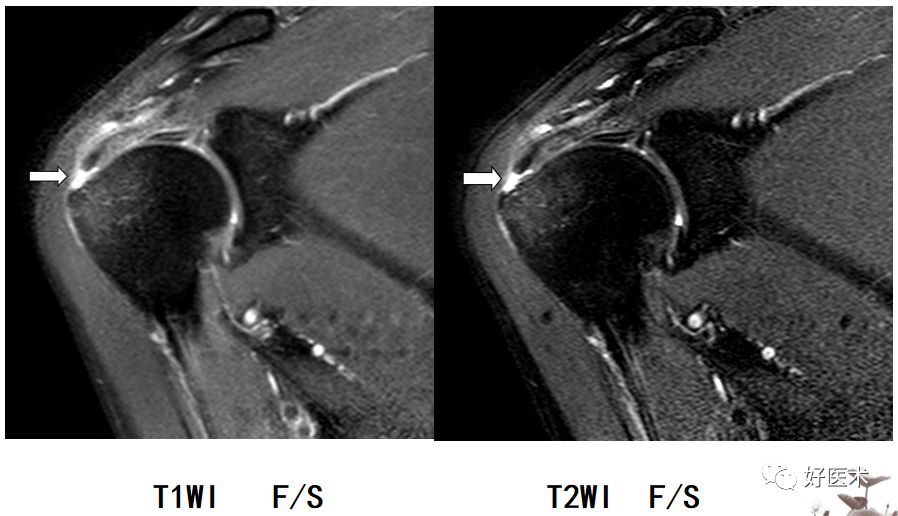

Bankart损伤的MR表现

-

三角形变钝

盂唇撕裂:关节盂唇软骨与盂缘可见线状高信号影并连续到关节面下

盂唇完全消失或盂唇明显移位

若盂唇损伤合并关节盂骨质损伤,称为骨性Bankart病变

骨性Bankart病变

MR间接关节造影1.5T轴位T1W脂肪抑制(TR=460s,TE=90s)